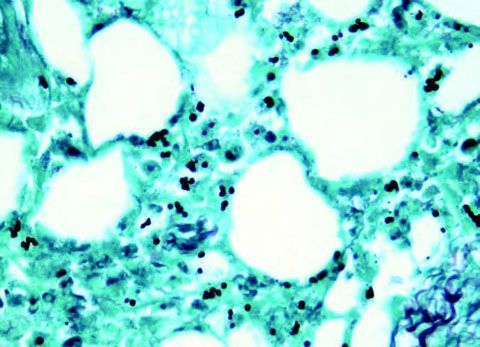

The patient's condition continued to deteriorate over 4 days, despite appropriate therapy; skin lesions, myopathy, and dyspnea worsened. Cultures of 3 skin biopsy specimens taken from the upper extremities revealed numerous budding yeast (C) that grew mold forms of Histoplasma capsulatum. Microscopy of a muscle biopsy specimen taken from the right lower limb demonstrated fungal yeast forms; it also showed type II fiber atrophy, which was likely secondary to long-term high-dose corticosteroid therapy. A urine test for Histoplasma antigen was positive (27.84 ng/mL).